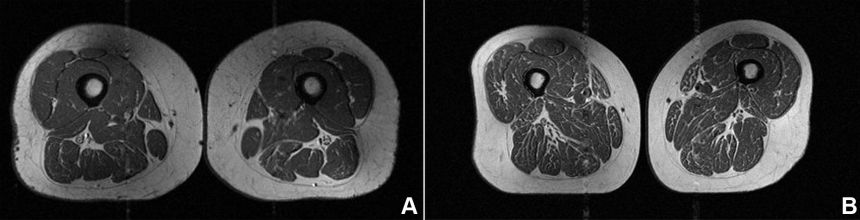

The diet of the woman on the left was 29.5% ultra-processed, and the diet of the woman on the right was 87.1% ultra-processed.

The image resembles a slice of well-marbled meat, reminiscent of a fine steak with abundant streaks of finely textured fat. But it’s not dinner. This is an MRI scan of the thigh of a 62-year-old woman who consumed 87% of her annual calories from ultra-processed foods. “This participant’s diet consisted primarily of cold cereal, chocolate … Read more